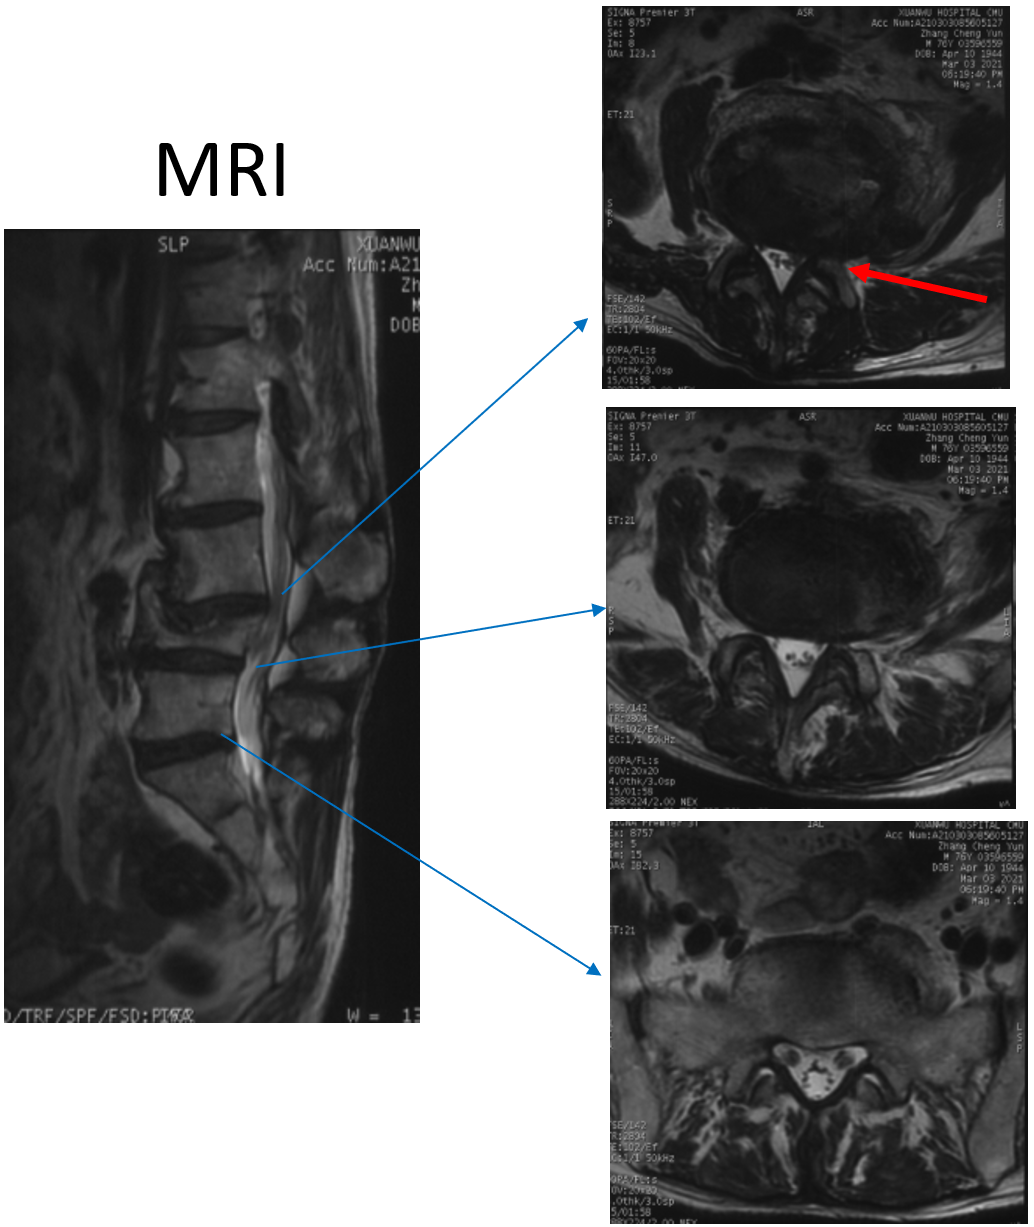

讨论主题:L4压缩骨折伴脊柱侧后凸畸形

影像资料:

腰椎侧后凸畸形

腰椎陈旧性压缩性骨折(L4)